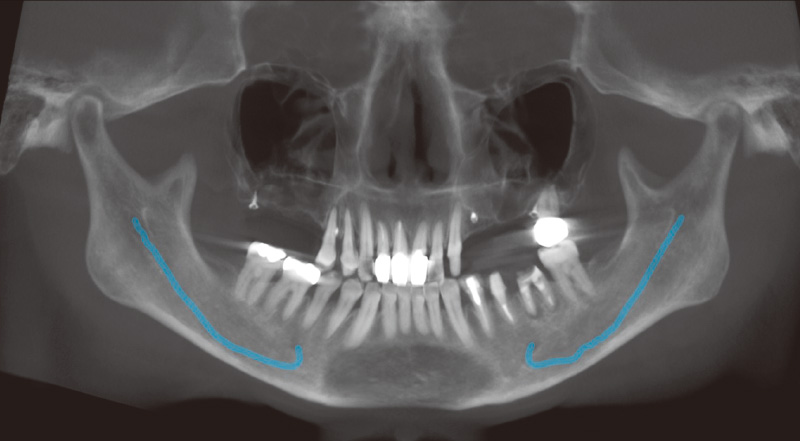

図2 再診時のパノラマX線画像。上顎に多数歯欠損が認められる。 -

図3 2024年2月再診時。趣味であるスキューバーダイビングを行う際、義歯が安定せず、マウスピースがうまく噛めないとのことで、再治療を希望された。 -